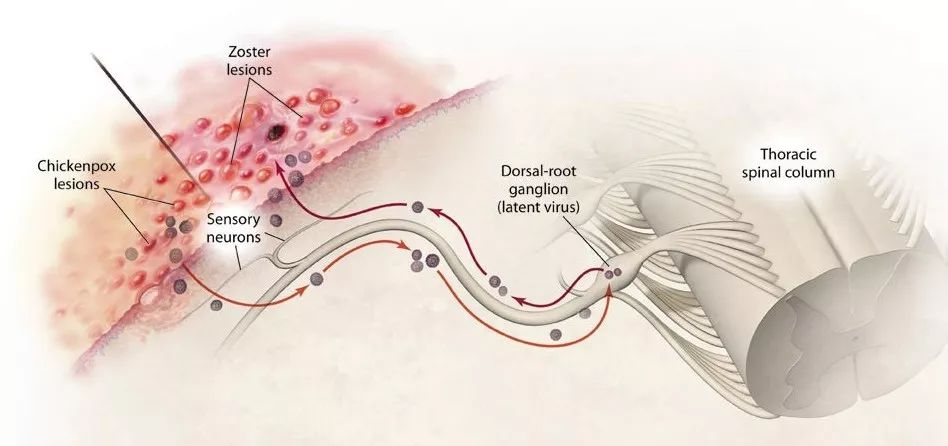

当VZV病毒首次攻破人体的免疫大军,感染人体之后,我们就长出了水痘。我们知道水痘常发生在婴幼儿和学龄前儿童身上,但请不要以为成年后就不会再长了。

唯一庆幸的是,水痘对现代医学来说早已不是什么大不了的事。无论是儿童还是成人,只要及时前往医院接受一到两周的治疗,就基本可以痊愈了。可当你以为烧退了,水痘脱痂了,身体全好了的时候,这种VZV病毒却仍未完全离开你的体内。

原来在治疗水痘的过程中,人体免疫系统确实把体内大多数的VZV病毒消灭掉。但仍会残留一些不能被血清中的抗体完全中和的VZV病毒。这些病毒发挥着自己天然亲近神经的特性,顺着皮肤的上皮感觉神经末梢不断逃离免疫大军攻击。最后,它们躲进了脊髓后根神经节的神经元或是颅神经的感觉神经节里,并在长期定居了下来。

不过,它们平日里就一声不吭地潜伏在那里,甚至一待可以待上几十年的光景。假设你在1-2岁得过水痘,这些病毒则会陪着你长大成人,看着你结婚生子,等待你逐渐老去。可别以为这病毒只是单纯地想跟你厮守一生,它们是在等待下一个疯狂肆虐的时机。等到你老了或者是因过度劳累,身体免疫力下降时,它们又不留情面地出来攻击你了。

3D版的水痘-带状疱疹病毒

据《2016 带状疱疹后神经痛诊疗中国专家共识》估计:60岁以上带状疱疹患者PHN发生率为65%,70岁以上带状疱疹患者PHN发生率为75%。当这些VZV病毒重出江湖时,它们会沿着我们的感觉神经轴突到达所支配的皮肤细胞,继而在细胞内增值引起疱疹。这样生成的疱疹沿一侧周围神经作群集带状分布。这也正是它叫做带状疱疹的原因。